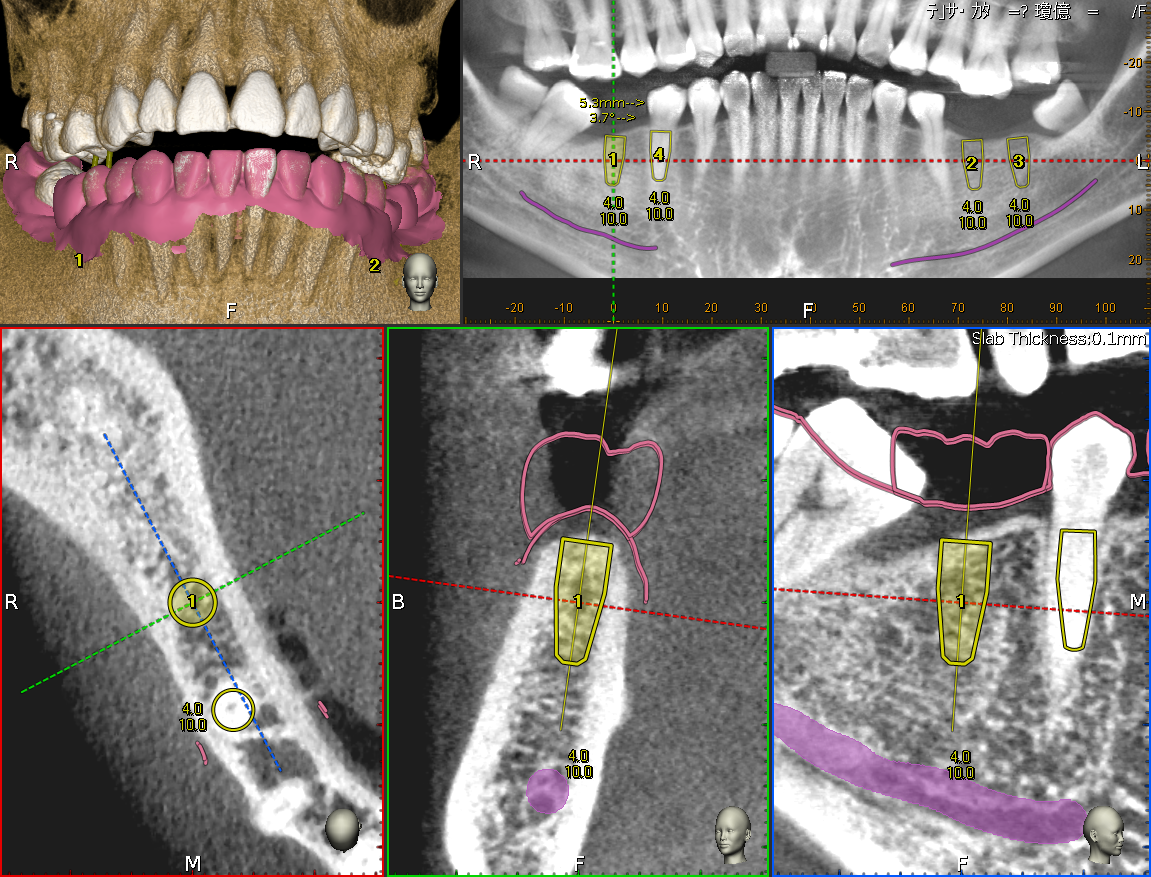

導航植牙,也叫做「4D動態導航植牙」,其實就是利用高科技來幫助我們更精準地完成植牙手術,簡單來說,就是在手術前會先幫你做電腦斷層(CT)、數位口腔印模,把你的骨頭、神經、血管、口腔等重要結構都看得很清楚,然後用電腦軟體中預先規劃未來假牙位置、植體植入的深度及角度,模擬出植牙的最佳路徑做定位,降低植牙療程中的誤差,有效提高治療的成功率並減少植牙後遺症,達到真正的數位植牙。

手術的時候,病人要戴上一個定位器,我們會用導航裝置即時追蹤手術器械的位置,就像開車有GPS一樣,可以確保植體放得又準又安全。這種方式特別適合骨頭條件比較差、空間有限,或者一次需要植多顆牙齒的患者,因為傳統方法有時候比較難拿捏得那麼精細。

將數位資料匯入專業植牙規劃軟體,在電腦上進行精密的「虛擬手術」,預先設定好植體的最佳位置、角度、深度。

使用植牙導航,手術資訊與數位檔案同步顯示在電腦畫面上,使醫生能更快速、精準、安全的將植體放到目標位置。

▲使用導航技術,可以手術當下即時反映出植牙鑽針的角度、深度、位置等資訊,精準定位植體位置。